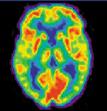

November 13, 2008 – An estimated 15.7 million patients received nuclear imaging procedures in the U.S. in 2007, in 7,320 hospital and nonhospital sites, according to a report by IMV Medical Information Division.